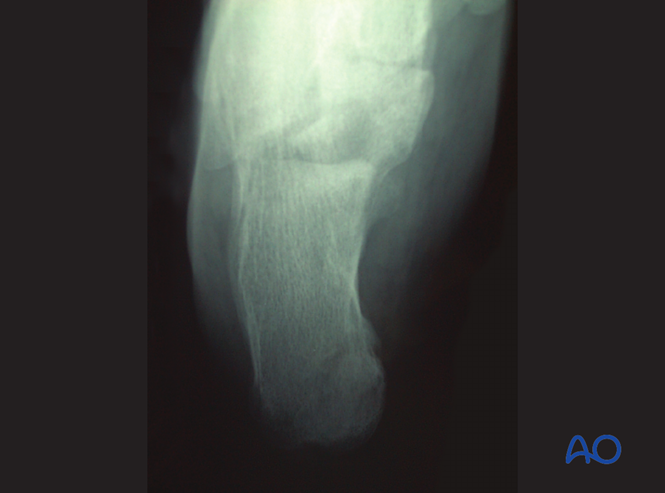

踝关节侧位片可显示跟骨后结节显著移位,并明确骨折是否累及距下关节(subtalar joint)或完全位于关节外。

图片

贝氏角(Böhler’s angle)

侧位X线测量贝氏角减小提示关节损伤及塌陷程度。正常值为25-40度,若角度>15度可考虑保守治疗。